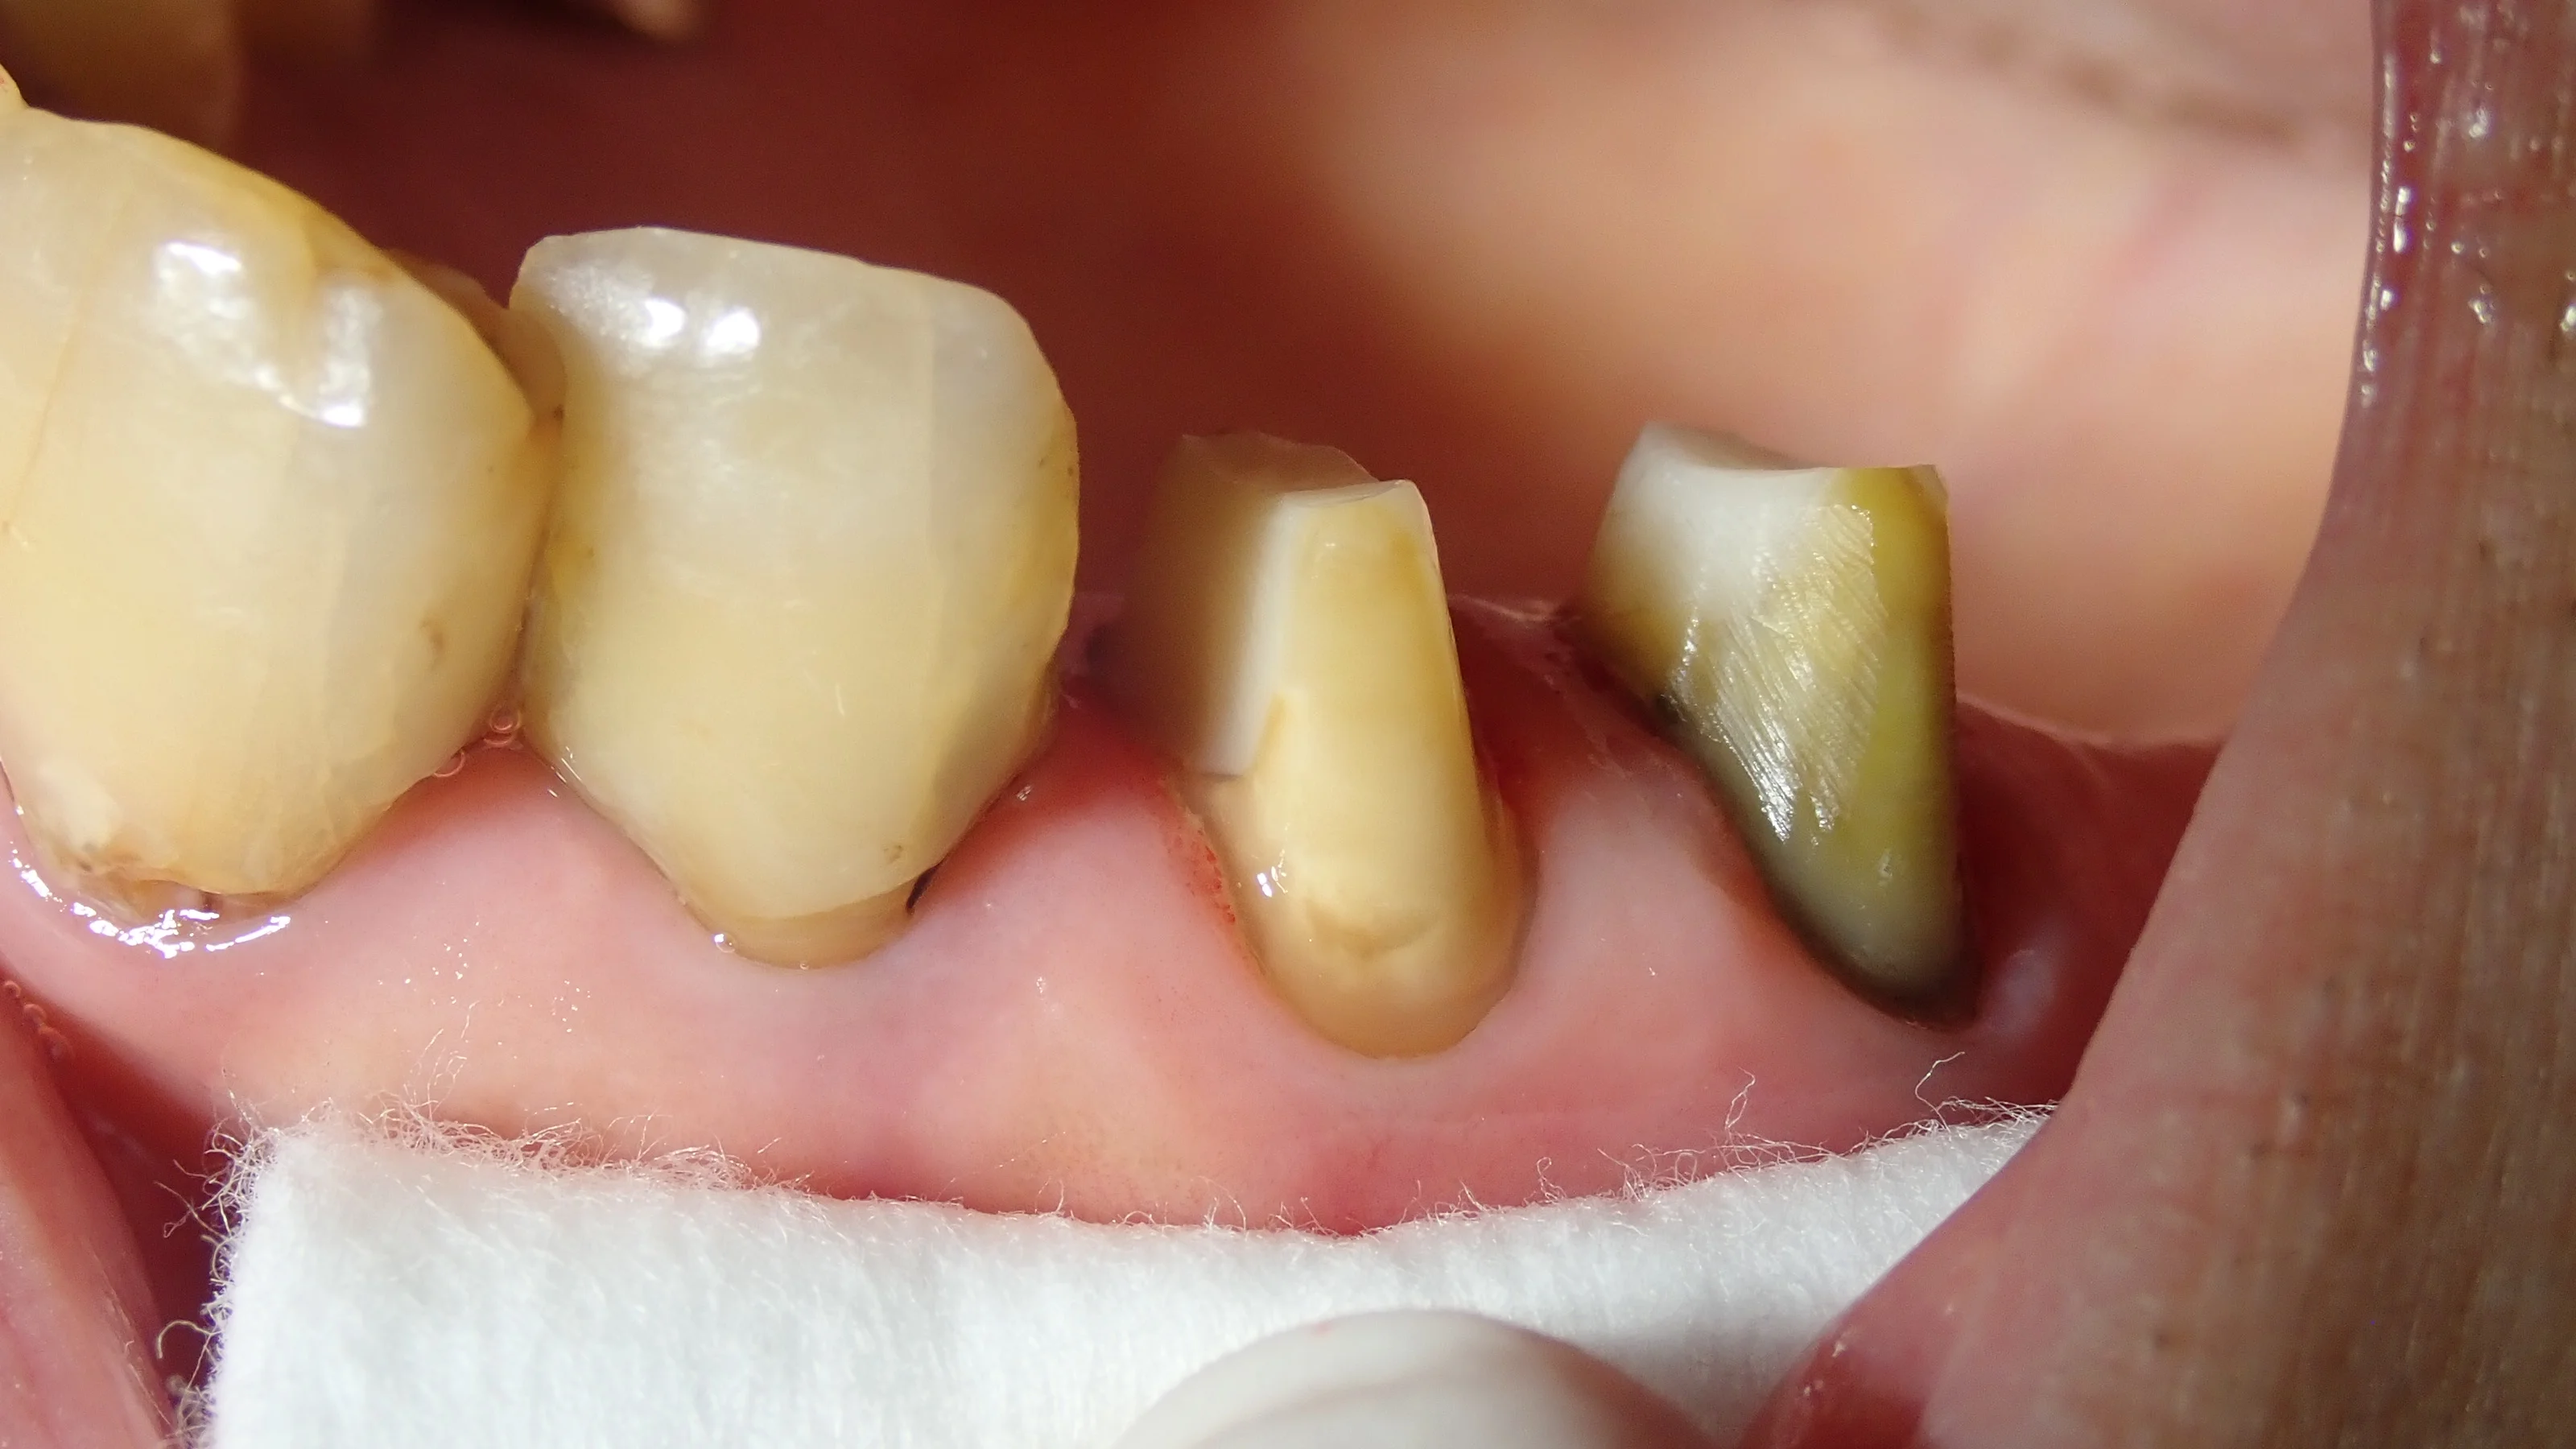

Set前の写真です。

横から見た図です。